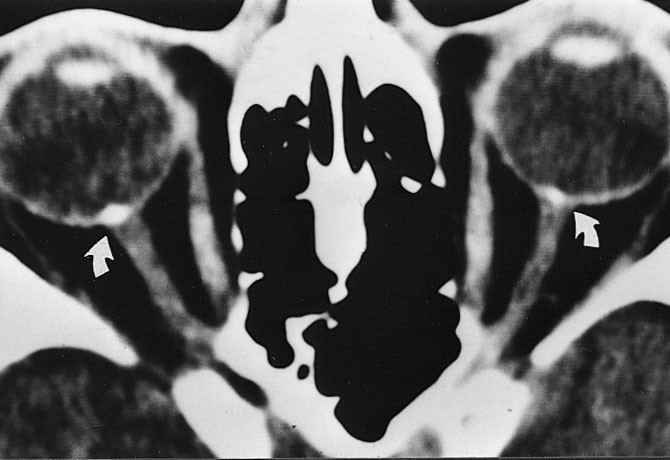

CT med koronalt og aksialt snitt er å foretrekke ved endokrin oftalmopati. Et karakteristisk CT-funn er en relativt symmetrisk forstørrelse, først og fremst av nedre og mediale rette øyemuskler. I 90 % av tilfellene kan det avdekkes patologiske forhold bilateralt, til tross for ensidige symptomer. Aksiale og koronale plan viser godt fordelingen og graden av muskelforstørrelse og forholdet til synsnerven ved orbital apex (8). Det er en relativ sparing av muskelsenen, mens det er særlig fortykket midtre og bakre del ved muskelbunten som er typisk og muliggjør differensiering fra myositt. Endokrin oftalmopati forekommer i 2 – 7 % av tilfellene av Graves sykdom, i aktiv fase med inflammasjon og lymfocyttinfiltrasjon i retrobulbært orbitalt vev, i utbrenningsfasen med fibroser. Et fokalt lavattenuerende område innenfor muskelbunten er et annet CT-funn som tyder på endokrin oftalmopati. Tidlig i forløpet finnes lymfocytisk infiltrasjon og fokal mukopolysakkaridavleiring, mens fettinfiltrasjon forekommer i den senere fasen. Andre hyppige funn ved Graves sykdom er ekspansjon av det orbitale fett, som presser orbitalseptum fremover og dermed strekker synsnerven.